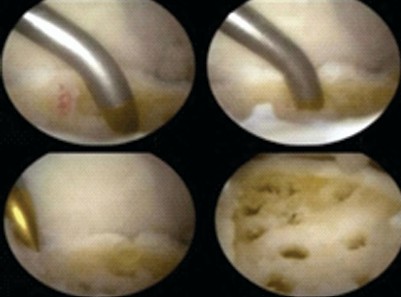

The anterior or posterior two-portal approach is selected based on the location of the osteochondral lesion of the talus (OLT). Patients undergoing the anterior approach were positioned supine position. An anteromedial and anterolateral two-portal approach was made (Fig. 1 and 2). Just medial to the tibialis anterior tendon helps define the anteromedial portal and the anterolateral portal just laterals to the peroneus tertius tendon. Arthroscopic microfracture is a reparative cartilage procedure performed under direct visualization to address OLTs (Fig. 3). For reference, Figure 4 shows osteochondral lesion over the talus.

Figure 3: Arthroscopic view of microfracture.

After diagnostic arthroscopy, identifying the OCD a shaver or curette was used to remove the unstable cartilage and subchondral necrotic bone. The sclerotic zone was completely debrided; the lesion is thoroughly debrided to remove unstable cartilage, exposing a stable rim of healthy cartilage and a clean subchondral base.

After diagnostic arthroscopy, identifying the OCD a shaver or curette was used to remove the unstable cartilage and subchondral necrotic bone (Fig. 5).

Figure 5: Intraoperative arthroscopic images.

The sclerotic zone was completely debrided; the lesion is thoroughly debrided to remove unstable cartilage, exposing a stable rim of healthy cartilage and a clean subchondral base. A microfracture awl or 1.4-mm Kirschner wire or a 2-mm drill through the portal was used to drill several holes in the base of the OCD of talus used to create multiple evenly spaced perforations (approximately 3–4 mm apart) into the subchondral bone, penetrating 2–4 mm deep. This induces bleeding from the underlying marrow cavity, forming a fibrin clot rich in mesenchymal stem cells and growth factors. The resulting clot provides a biodegradable scaffold that (a) fills the OCD, (b) supports mesenchymal cell infiltration and chondrogenic differentiation, (c) has appropriate porosity/mechanics, and (d) degrades at a rate matching matrix deposition.